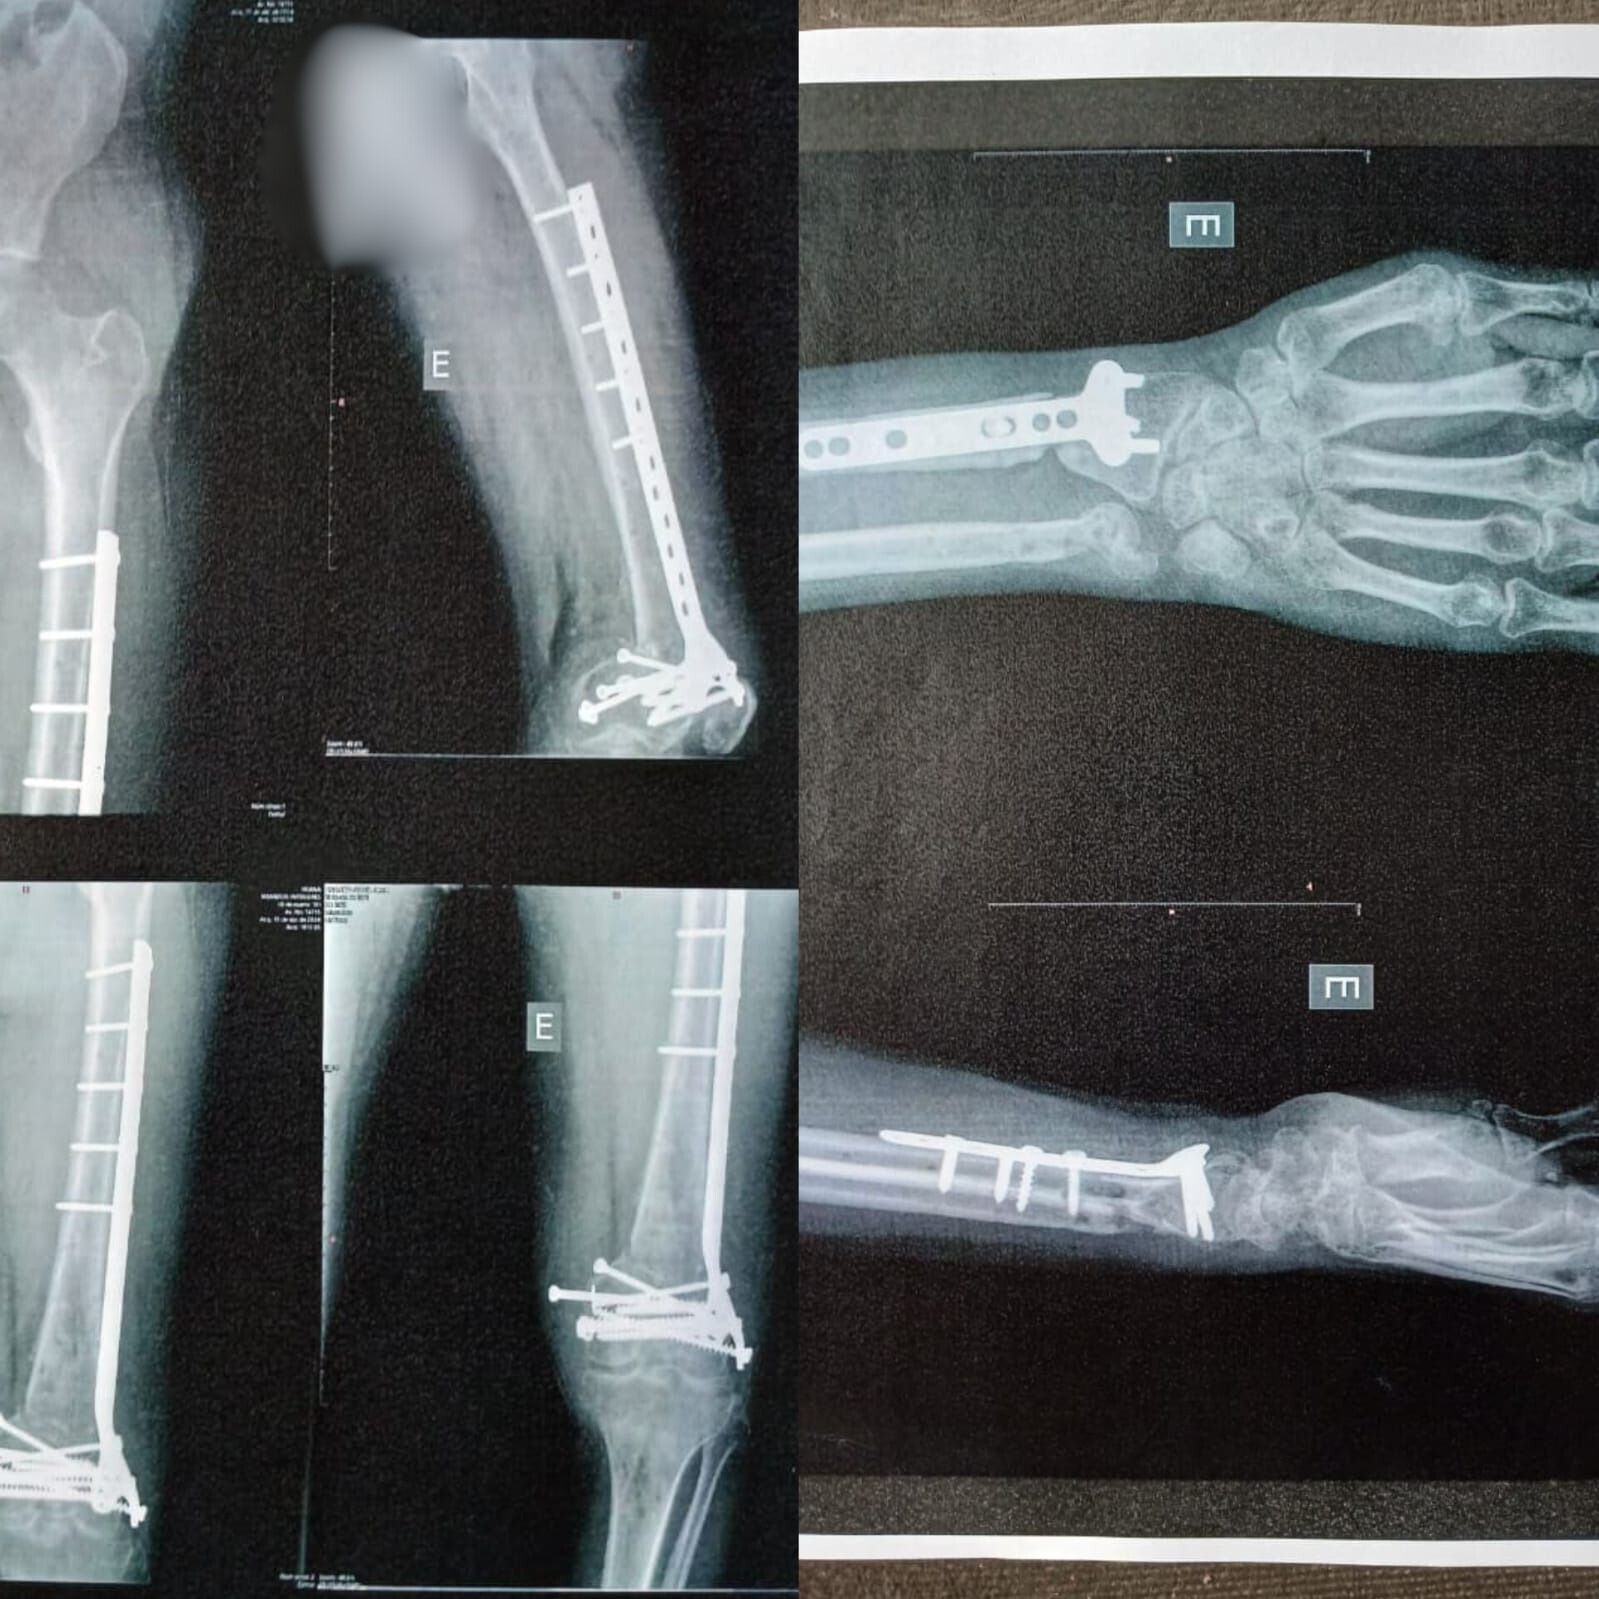

Toda essa luta e os diversos “bicos” sofreram um doloroso e quase fatal revés em novembro de 2023. A caminho do trabalho em sua motocicleta, Adriano foi atropelado por um caminhão.

O acidente resultou em diversos ossos quebrados, perda de parte do nariz e um coágulo na cabeça. Com uma das pernas esmagada e permanentemente paralisada, ele não pôde mais seguir com a vida ativa que levava.